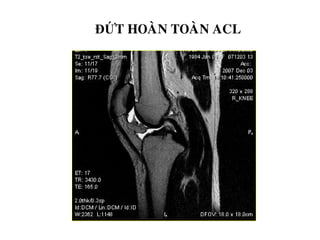

ĐỨT HOAØN TOAØN ACL

- Maát lieân tuïc hoaøn toaøn, khoâng thaáy daây chaèng treân

phim.